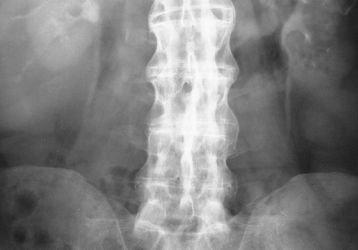

Болезнь Бехтерева или анкилозирующий спондилит: симптомы, лечение, что это такое

Что такое болезнь Бехтерева или анкилозирующий спондилит, причины, характерные симптомы, диагностика. Формы проявление и лечение болезни Бехтерева.